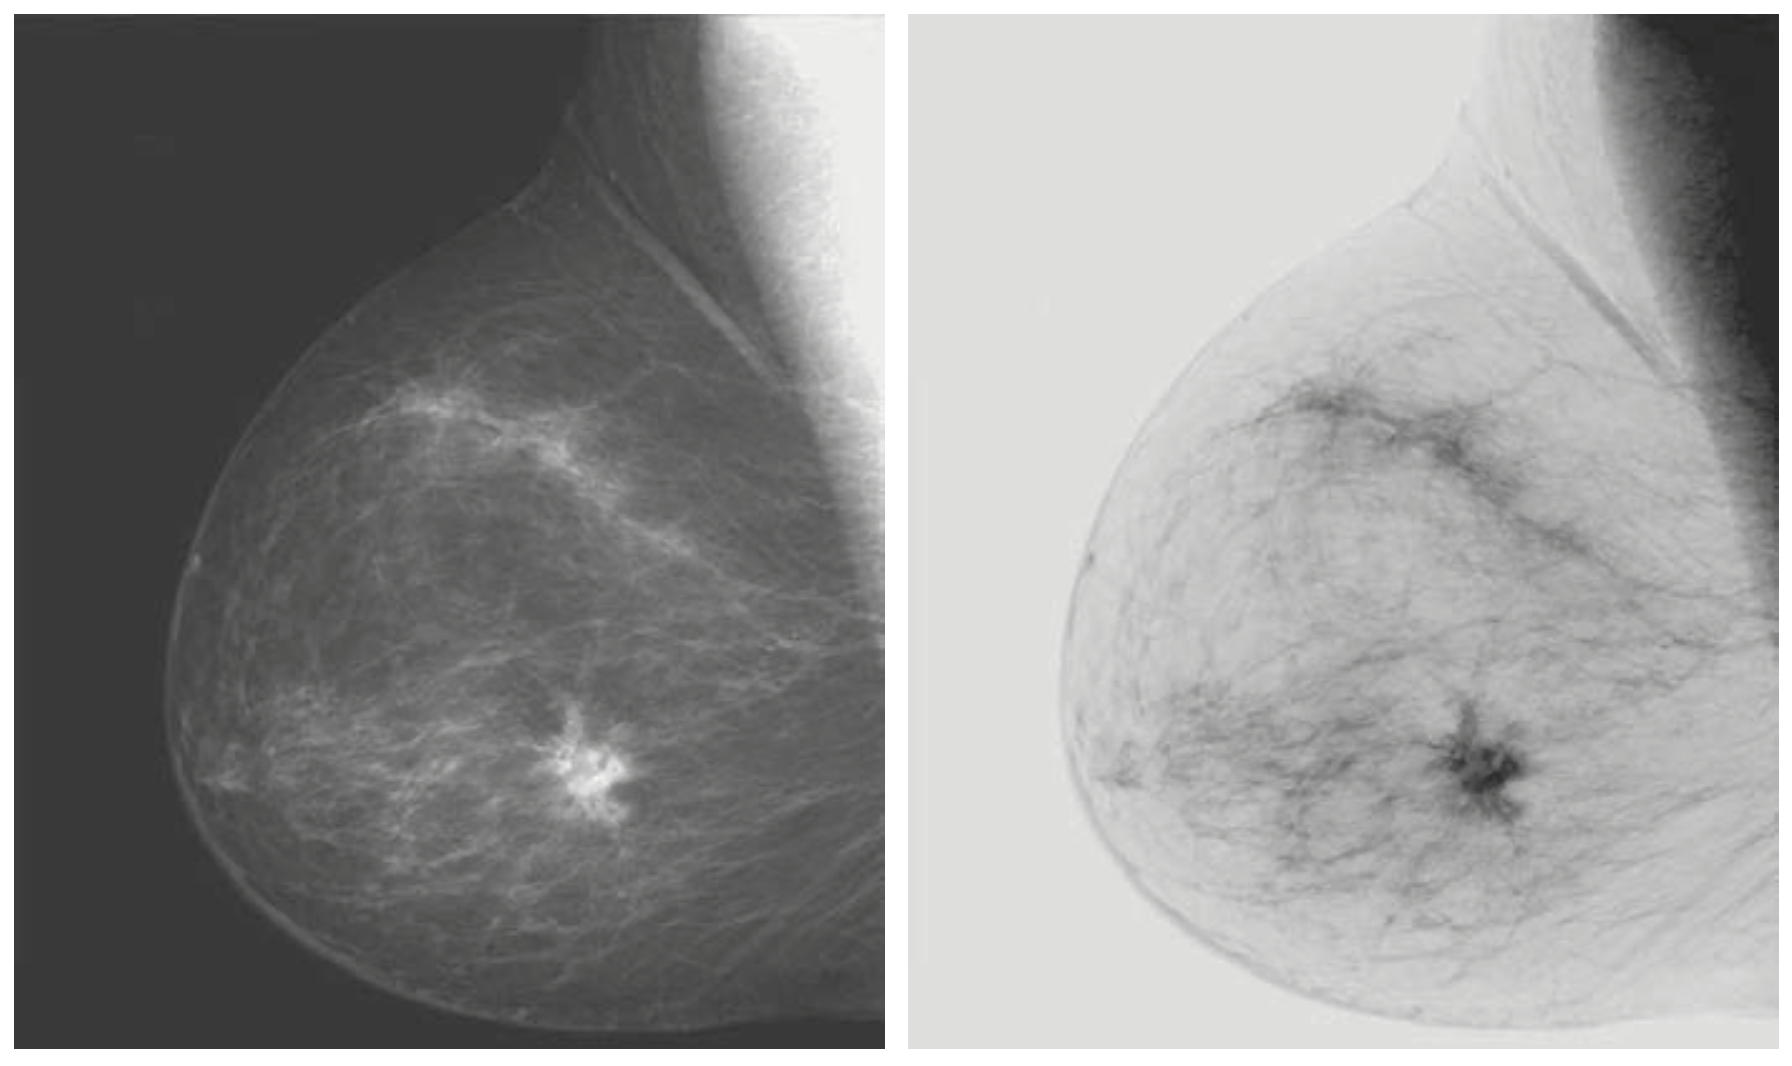

이를 통해서 위와 같은 영상을 얻을 수 있습니다. 왼쪽 영상에 비해서 오른쪽 영상에서 조직의 위치를 더 강조하고 있는 것을 볼 수 있습니다. 사실 이와 같은 변환은 조직 위치의 강조도 있지만 여러분들이 프린트를 생각해보시면 됩니다. 프린트할 때 검은색이 대부분이라면 프린터기는 기본적으로 검은색 색상을 대부분 사용해야 합니다. 그러면 잉크가 더 빨리 떨어지겠죠? 그다음으로는 검은색은 인쇄된 뒤 다른 색에 쉽게 침범할 수 있기 때문에 모니터로 보는 결과와 많이 달라집니다.